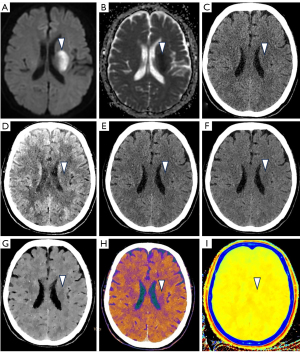

Using conventional images from the initial CT scans (see Figure 2), regions of interest (ROIs) were manually defined at the sites of ischemic lesions and the corresponding normal brain on the opposite side, with one ROI assigned to each site.

Figure 5 illustrates a clinical case of a patient with AIS, providing a comparison between traditional images and spectral images.